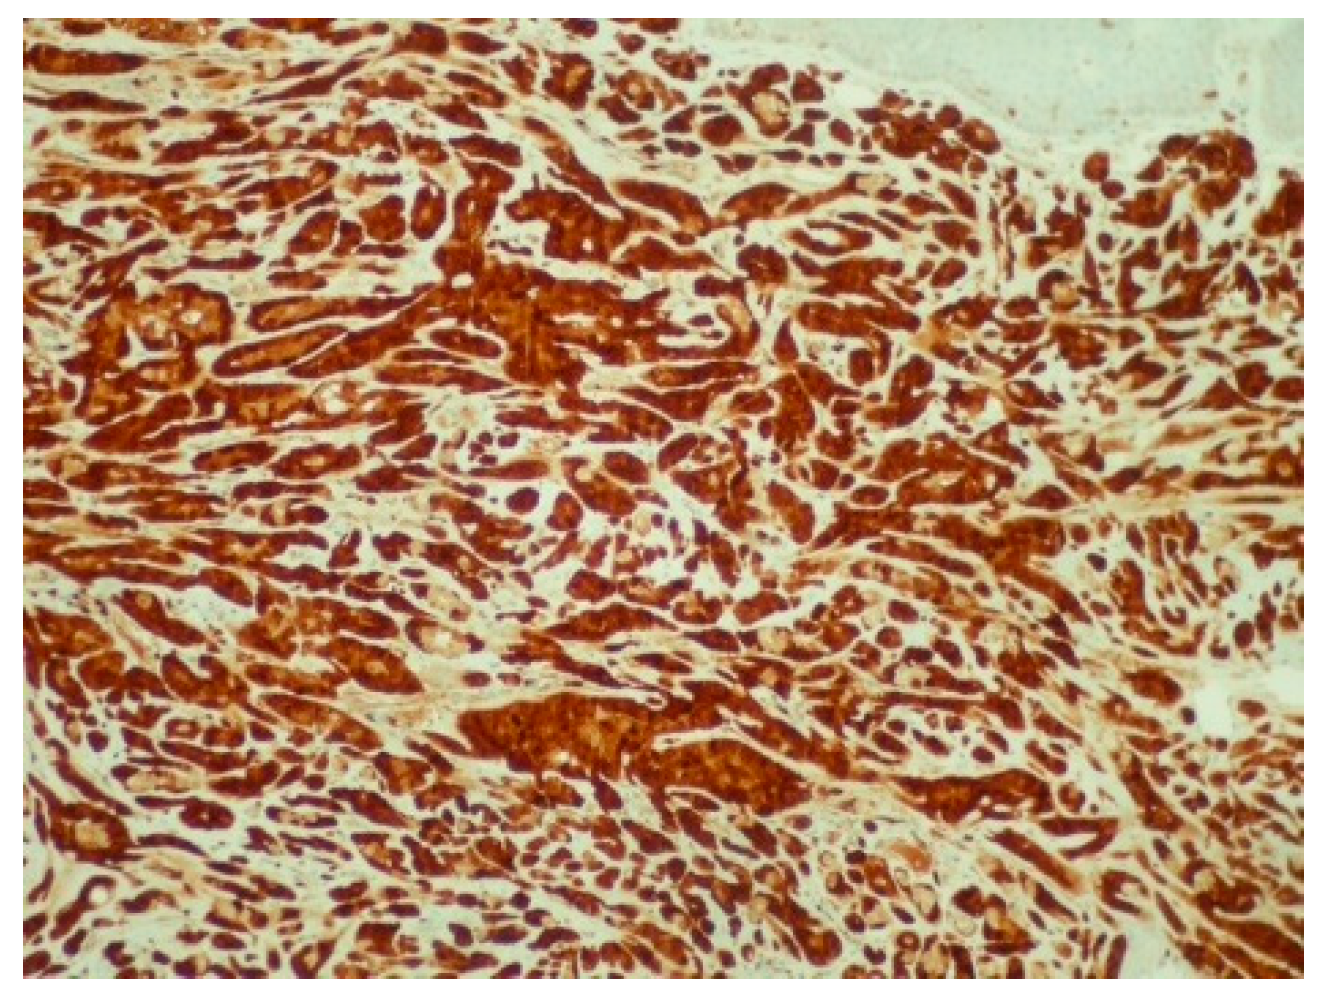

2. Case Presentation

3. Discussion